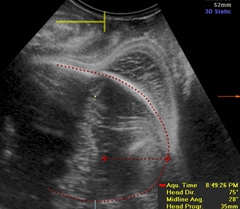

GE公司的SonoVCAD labor技术是基于三维容积超声的计算机辅助产程监测软件。利用三维超声多平面成像技术,可同时显示相交平面,增加了更多信息,使得测量的切面更为准确,重复性佳[5]。软件可在三维容积数据的不同平面自动测量出相应的胎头方向角(图1)、胎头进展角(图2)、胎头下降距离(图3)及中线角(图4)这四个参数,并在产程中动态观察各参数的变化,利用软件记录产程的全过程(图5),从而监测第二产程进展。

图2. 在A平面,从耻骨联合到胎头边缘画一条切线,胎头进展角为这条切线和耻骨联合中间部分的水平线的夹角